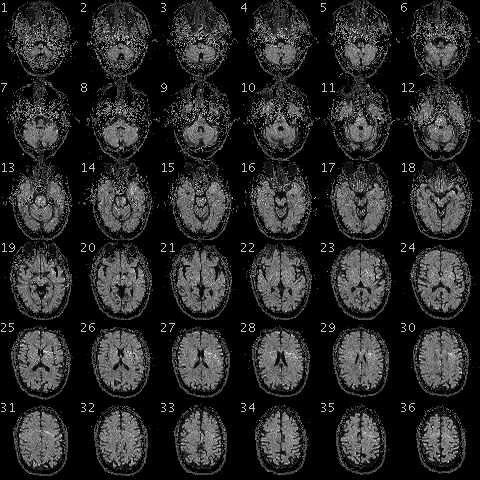

기능자기공명영상법(fMRI) 스캔을 통해 얻은 데이터는 분석 전에 여러 단계의 전처리 과정을 거친다. 스캐너는 각 TR(반복 시간)마다 피험자의 머리에 대한 3차원 볼륨 이미지를 생성하며, 이는 각 복셀의 강도 값 배열로 구성된다. 여러 시간대에 걸쳐 촬영된 이 볼륨들을 결합하여 4차원 볼륨 데이터를 만들고, 이것이 분석의 시작점이 된다. 전처리 과정은 데이터의 노이즈를 줄이고 분석의 정확도를 높이는 것을 목표로 한다.전처리의 첫 번째 단계는 일반적으로 슬라이스 타이밍 보정(slice timing correction)이다. MR 스캐너는 뇌의 각 슬라이스를 약간 다른 시간에 촬영하기 때문에, 각 슬라이스는 서로 다른 시점의 뇌 활동을 나타낸다. 슬라이스 타이밍 보정은 모든 슬라이스의 시간 기준을 동일하게 맞춰주는 과정이다. 이는 각 복셀의 시간 경과 데이터가 부드러운 곡선을 그린다고 가정하고, 샘플링되지 않은 시점의 값을 보간하여 계산한다.